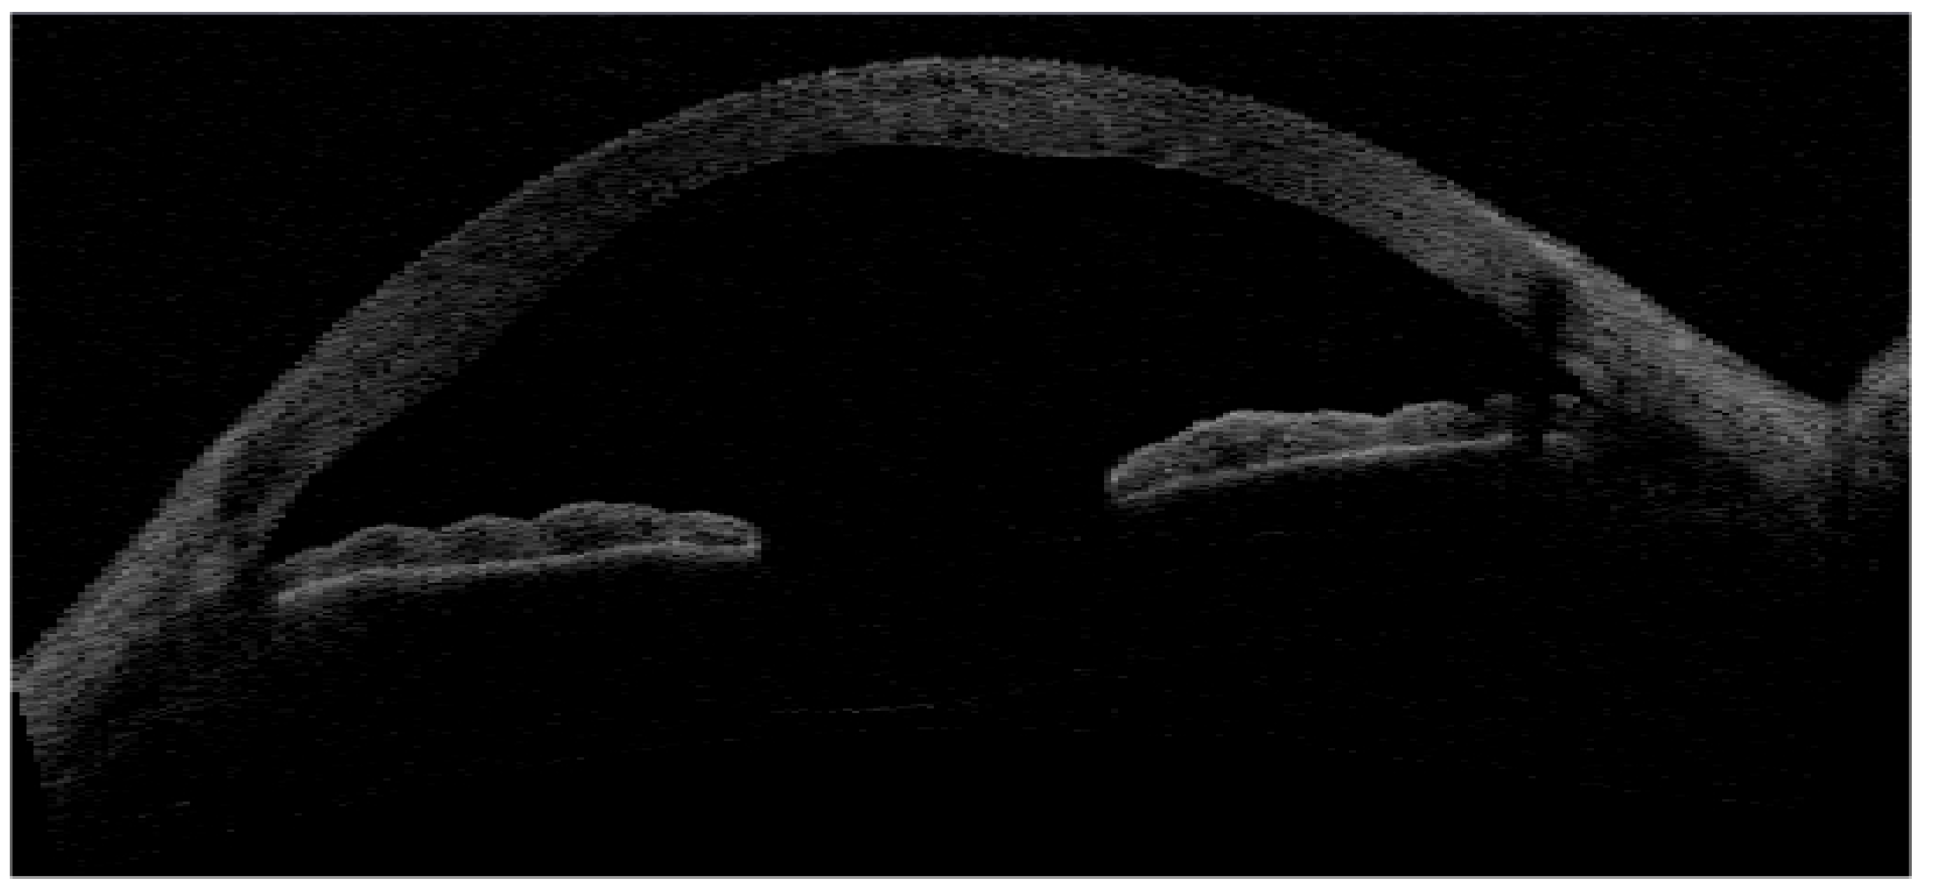

- Liang, Q.; Pan, Z.; Zhou, M.; Zhang, Y.; Wang, N.; Li, B.; Baudouin, C.; Labbé, A. Evaluation of optical coherence tomography meibography in patients with obstructive meibomian gland dysfunction. Cornea 2015, 34, 1193–1199. [Google Scholar] [CrossRef]

- Yoo, Y.S.; Na, K.S.; Byun, Y.S.; Shin, J.G.; Lee, B.H.; Yoon, G.; Eom, T.J.; Joo, C.K. Examination of gland dropout detected on infrared meibography by using optical coherence tomography meibography. Ocul. Surf. 2017, 15, 130–138. [Google Scholar] [CrossRef]